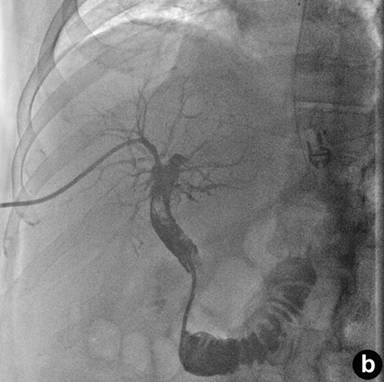

The patient returned three weeks later with near-syncopal symptoms, melena, and hematochezia. As the patient was exhibiting signs of intra-luminal bleeding, his first line diagnostic method was endoscopy which had to be repeated the following day due to clotted blood in the stomach. An additional 9 units of packed red blood cells were transfused. A tagged red-blood cell scan demonstrated bleeding localized to the proximal small bowel, and angiography demonstrated a right intra-hepatic artery pseudoaneurysm (Figure 2ab). The appearance of this pseudoaneurysm was small and intrahepatic and there was no extravasation of contrast or communication with the biliary tree. However, this was the likely source of bleeding and therefore we proceed to embolize it expeditiously. The patient had two straight 2 mm microcoils and two vortex microcoils of 3 ad 3.3 mm placed for selective embolization. After the procedure, the patient’s hematocrit stabilized, and he had no further episodes of hypotension or gastrointestinal bleeding. He is currently doing well without any sequelae nine months after surgery.

Figure 2. Right intra-hepatic artery pseudoaneurysm. Note the proximity of the percutaneous transhepatic cholangiography catheter (a.) to the location of the pseudoaneurysm (b.). |